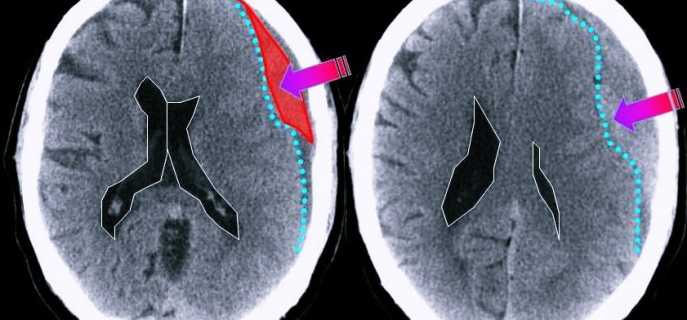

Основными причинами травматического субдурального кровоизлияния является травматизация головного мозга и повреждение интракраниальных вен. Важнейшими диагностическими элементами являются КТ и МРТ, причем современные специалисты больше предпочитают компьютерную томографию, с помощью которой быстро обнаруживается однородная серповидная зона увеличенной плотности.

Спустя некоторое время гематома начинает разуплотняться, распадаются кровяные пигменты, поэтому по уровню плотности через несколько недель после травматизации ее уже сложно отличить от здоровой мозговой ткани. Диагностика в данной ситуации базируется на медиальном смещении латеральных отделов и на обнаружение следов сдавливания бокового желудочка.